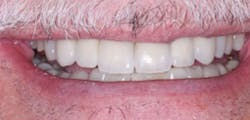

Figure 2: A comparison of PFM with all-ceramic restorations. Base your own decisions on both history and the research on all-ceramic restorations as summarized in the state-of-the-art information in this article.